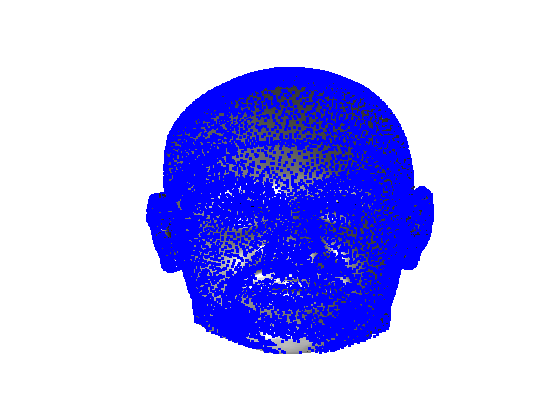

Following this, OSNR ICP iterates over a set of decreasing mesh stiffnesses (typically 10), until the registration between the template and the scan is below some error or a maximum number of iterations is reached. Figure 28 shows a selection of template warp results. The template appears to be accurately warped onto the scan, at least in the normal direction of the surfaces, it is not possible to see error tangential to the surface. Furthermore, we have noted errors on some scans on the ears. To improve these we need a method of automatically landmarking the ears, which is an area for further work.

|

|

|

|

|

|

|

|

The first two modes of head variation are shown in figures 29 and 30. These include the cranial height / facial angle mode and the (almost) pure size mode, as seen in the sagittal profile model.